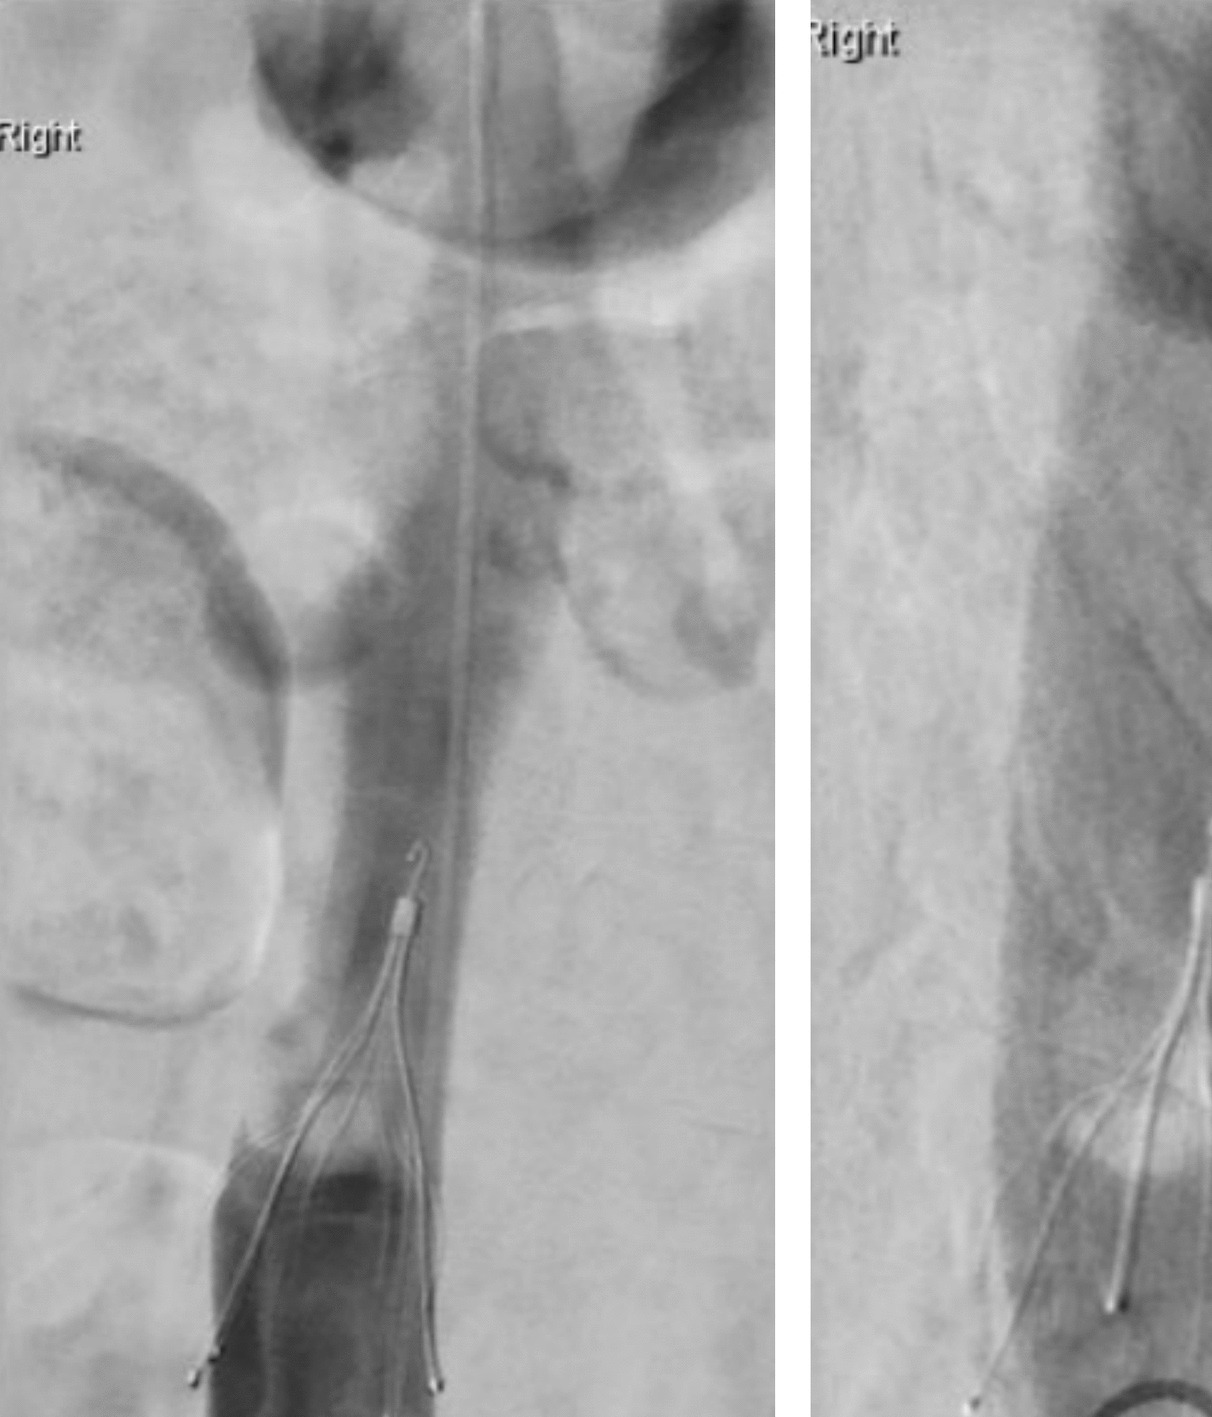

The inclusion of both mechanical and pharmacological VTE prophylaxis in our protocol is a deliberate design feature of this protocol, initially based on theoretical considerations outlined in Rosen’s Atlas of Abdominal Wall Reconstruction (1st edition, Chapter 15, page 250), which suggests that increased intraabdominal pressure from progressive insufflation may predispose patients to venous stasis and thromboembolic events [20]. This physiological rationale formed the basis of our early decision to include IVC filter insertion alongside weight- and renal-adjusted prophylactic low molecular weight heparin (LMWH), initiated at week T-5 before PPP commenced (Fig. 3).

Fig. 3

CT reformatted in the sagittal plane showing pneumoperitoneum and IVC filter

This strategy was further substantiated by our own institutional experience during the initial implementation phase. In a number of cases, thrombus was discovered within the IVC filter at the time of intended postoperative retrieval, with an example shown in Fig. 4. As a result, filters were not removed, and patients were commenced on therapeutic-dose LMWH, followed by a DOAC for a further two months in line with local protocols for provoked DVT [21, 22].

Fig. 4

Post-operative cavogram at time of attempted IVC filter removal, demonstrating filling defect which is significant clot

The finalised protocol includes preoperative placement of an IVC filter at week T-5, followed by continuous prophylactic LMWH throughout both the preoperative and postoperative periods. Inpatient assessment for IVC filter retrieval is routinely conducted during the first postoperative week, ideally prior to discharge. In cases where thrombus is identified within the filter, a defined therapeutic escalation pathway is initiated, involving temporary retention of the filter, commencement of therapeutic-dose LMWH, and delayed retrieval after approximately four weeks. If the filter is successfully removed and no thrombus is present, patients continue prophylactic-dose LMWH for 28 days post-removal to mitigate ongoing thromboembolic risk.

To our knowledge, no published PPP protocols incorporate such a comprehensive approach to VTE risk stratification and management. This component of our pathway addresses an important, but often neglected, perioperative risk, ensuring that both mechanical protection and pharmacological prophylaxis are sustained throughout the highest-risk period.

The development of this protocol was not purely theoretical. Iterative refinement was informed by direct clinical experience, including the discovery of thrombus within IVC filters at the time of planned removal. These observations prompted the creation of a formalised VTE management pathway, emphasising the importance of combining mechanical protection with pharmacological prophylaxis and escalation where necessary.

However, several key differences justify our more conservative approach. At our institution, patients referred for CAWR typically engage with a structured programme involving obesity management as described earlier. Our use of PPP is structured only when loss of domain is judged as severe. Our preferred way of managing patients is weight loss and fitness interventions, with botox as an adjunct, and PPP only in those situations where it is judged by MDT meeting that closure (even with component separation) would lead to high intraabdominal pressures in the post-operative phase. Additionally, our institutional experience, particularly with cases of thrombus formation identified at IVC filter removal (as demonstrated in Fig. 4), has led to an understanding of the heightened thromboembolic risk associated with the PPP procedure in our specific patient cohort. Insertion of the catheter and index insufflation is performed in hospital, with subsequent insufflations performed in a Surgical Assessment Unit (SAU) in an ambulatory fashion.